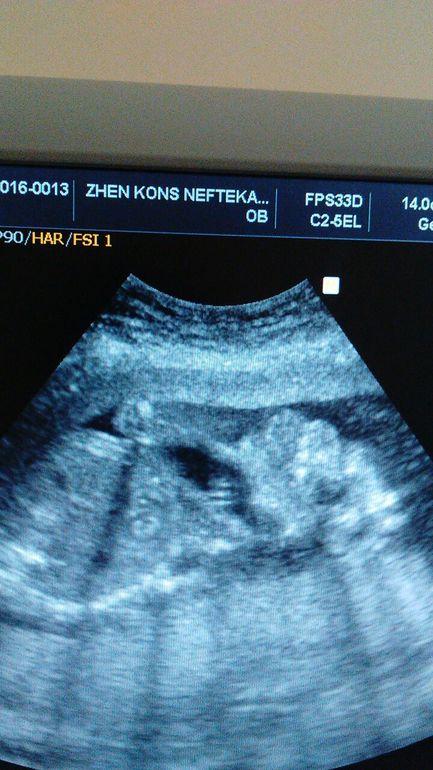

Это пальчики, другой палец после разделения